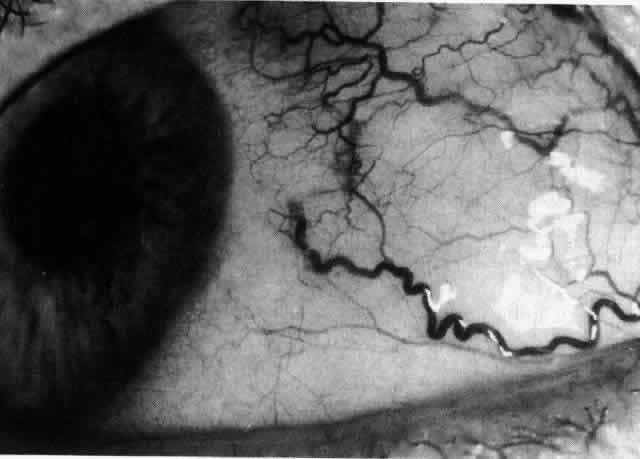

The characteristic features of necrotizing scleritis on fluorescein angiography are hypoperfusion and, eventually, nonperfusion of the vascular networks (Figs. 40 through 43).26 The initial changes are on the venous side of the capillary network; the transit time of the dye increases even if the eye is red and congested. If the disease process persists or has been present for a long time, thrombosis and permanent vaso-occlusive changes occur. These vessels (or the occluded capillary network) are bypassed by the opening of anastomotic channels. New vessels in a granuloma give rise to deep intrascleral leakage of dye (see Fig. 43). Conjunctival and episcleral involvement by the destructive change is late but is always preceded by vaso-occlusive changes that can sometimes be detected with use of the red-free light on the slit lamp (Figs. 44 and 45).

Fig. 41. Late stage of fluorescein angiogram adjacent to the site of necrosis in the same patient as in Figure 40. Although the eye is uniformly congested, the area near the necrosis shows vascular shutdown, whereas the rest of the conjunctiva and episclera is normally perfused.

Fig. 42. Late arterial phase of fluorescein angiogram in a patient with necrotizing scleritis. All the vessels except the main trunk and the vessels around the limbal perforating vessels are occluded and remain unperfused throughout the angiogram.

Fig. 43. Late venous phase of angiogram of a patient with necrotizing scleritis showing late deep leakage from vessels on the surface of the sclera and leakage of the capillary network at the limbus and the vessels draining it, together with poor or absent perfusion of the remaining vessels.